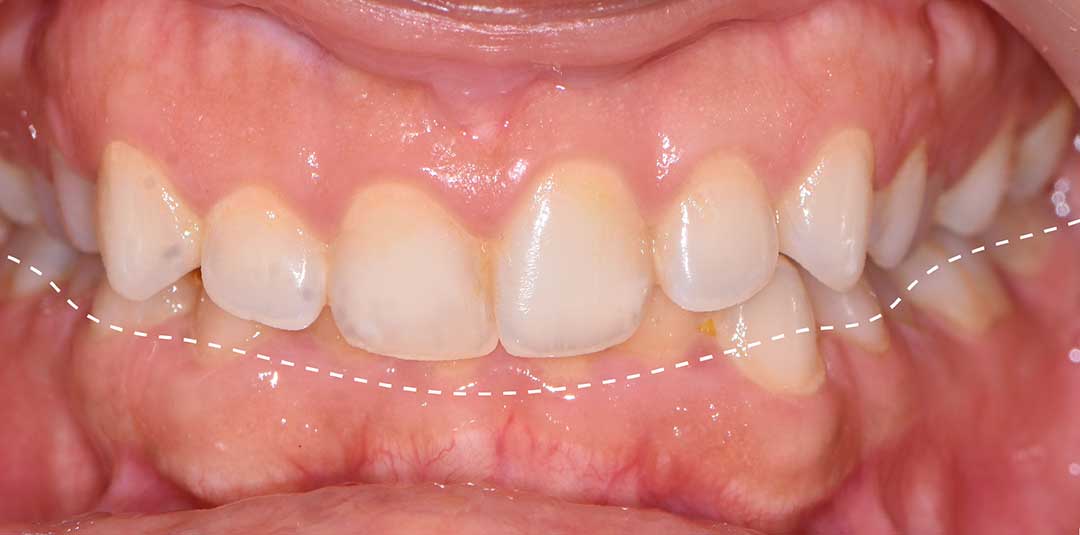

Beautiful Smiles

by Dr. Paolo Bellini